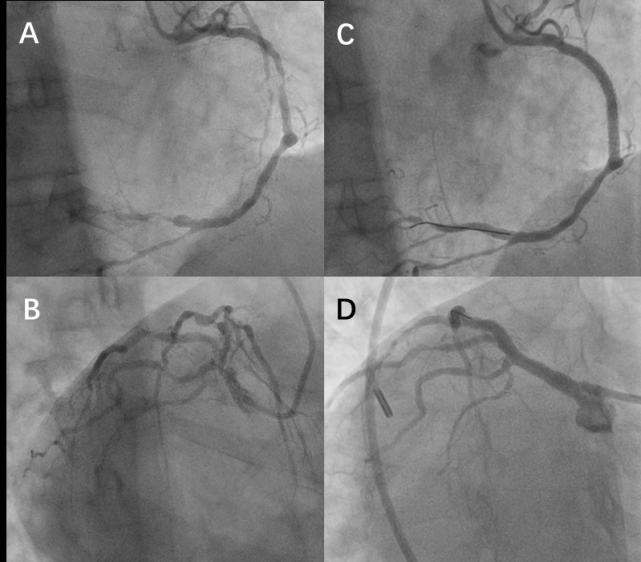

右位心影像图片,右位心心电图图片

只听说过镜面右位心?界叔这就带你亲眼见识!